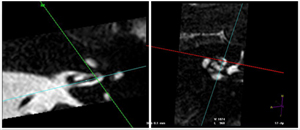

MRI imaging of the inner ear